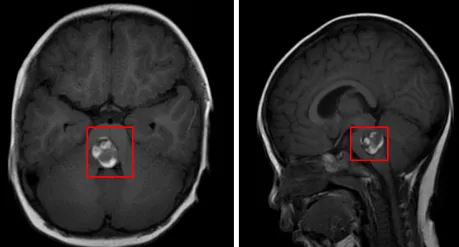

头颅核磁共振检查的结果很快就出来了:第四脑室底部占位性病变,考虑室管膜瘤可能性大。影像学特征提示肿瘤与脑干解剖关系密切,存在潜在的手术风险。

我们很快接受了第一次开颅手术。术前谈话时,医生指着影像片子向我们解释,肿瘤位置很深,位于第四脑室底部,紧贴着脑干,要实现完全切除的风险很高,术中稍有偏差就可能损伤重要的神经功能。